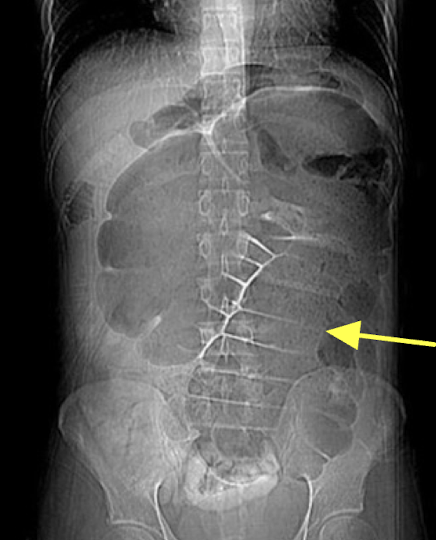

KUB (kidney, ureter & bladder)

XRAY optimized to assess the urogenital system ± GI system

Abdominal Radiograph

IVP (IV pyelogram)

XRAY using IV contrast material to assess kidney, ureters and bladder (less commonly used)

*CT Urogram is more common for assessing flank pain

Abdominal Radiograph

CT urography

CT scan using an IV contrast material to assess kidney, ureters, and bladder

Abdominal Radiograph